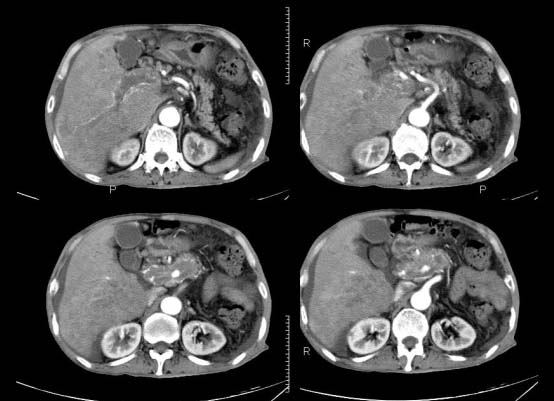

以下是引用杀毒软件在2010-3-30 18:11:00的发言:[br]考虑---hcc侵犯侵犯周围组织〔胰腺、胆管、肠系膜上动静脉〕伴门脉、下腔静脉癌栓形成、动-静脉瘘、肝门、腹腔动脉周围淋巴结转移可能性大、腹水。

以下是引用pujunzhi在2010-3-31 8:45:00的发言:[br]支持 肝癌并多发肝内转移,胰头、肝门、腹腔动脉周围淋巴结转移,下腔静脉癌栓形成,肝硬化、腹水。

以下是引用jsgdoctor在2010-3-30 20:42:00的发言:[br]考虑---hcc侵犯侵犯周围组织〔胰腺、胆管、肠系膜上动静脉〕伴门脉、下腔静脉癌栓形成、动-静脉瘘、肝门、腹腔动脉周围淋巴结转移可能性大、腹水。